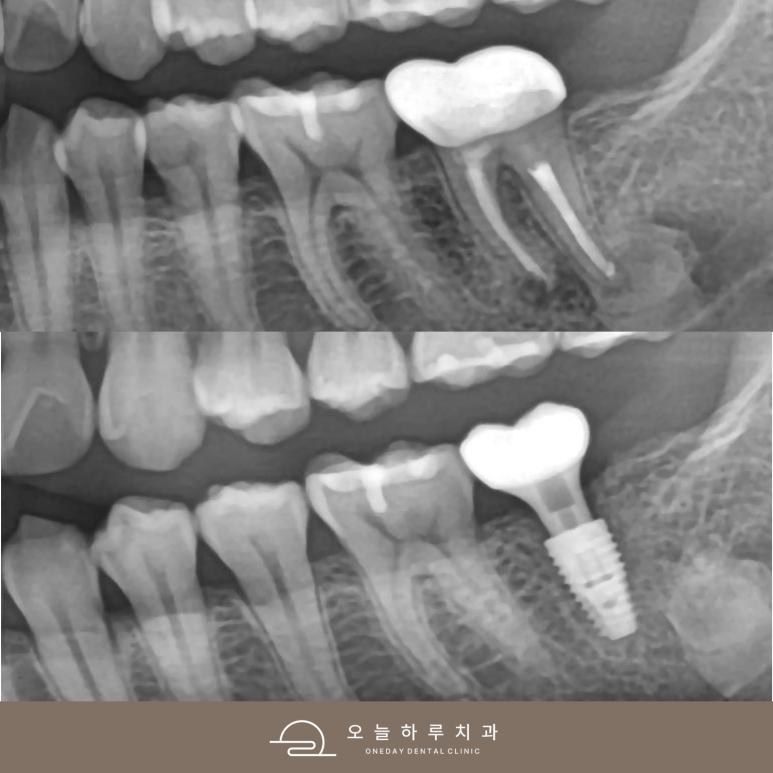

(#37 임플란트 치료 사례)

이번 환자분은

왼쪽 아래 어금니 (#37)에

👉 강한 통증을 느끼고 내원하셨습니다.

검사 결과,

✔ 이미 신경치료 + 크라운 치료가 되어 있었고

✔ 치아 뿌리 끝에 큰 염증이 형성된 상태였습니다

👉 이런 경우는 흔히

**“재발성 치근단 염증”**이라고 합니다.